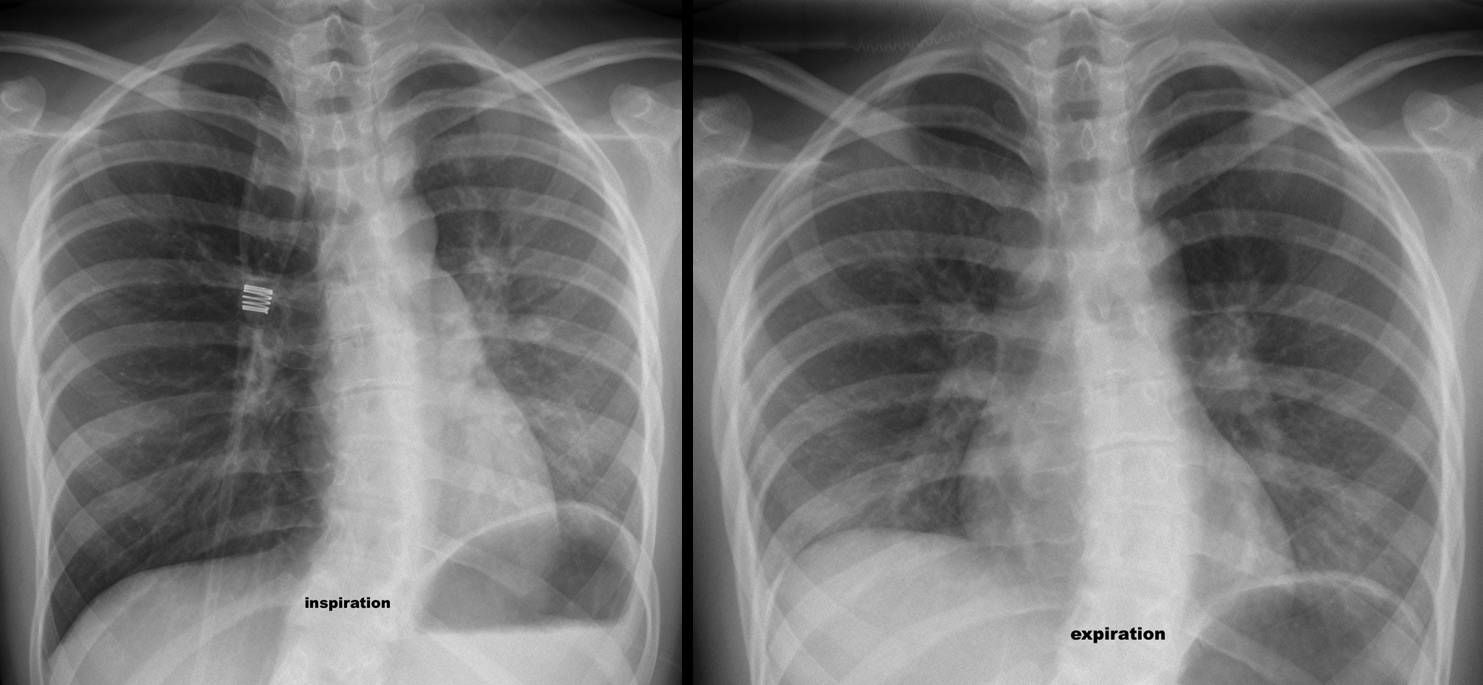

One of the common causes of respiratory symptoms in children is foreign body aspiration. Pneumonia recurring at the same location in the lung can indicate chronic aspiration of a foreign body. Radiological studies in such cases are of immense importance. Holzknecht sign is found on radiography in chronic cases of foreign body aspiration. On expiration, the affected lung becomes pneumatic due to occlusion at the level of bronchi. This results in an ipsilateral downward push on the diaphragm by the lung. On inhalation, the midline shifts to the affected side which is referred to as the Holzknecht sign. Reference: http://oftankonyv.reak.bme.hu/tiki-index.php?page=Thorax Image via: https://blog.myesr.org/caceress-corner-case-58/